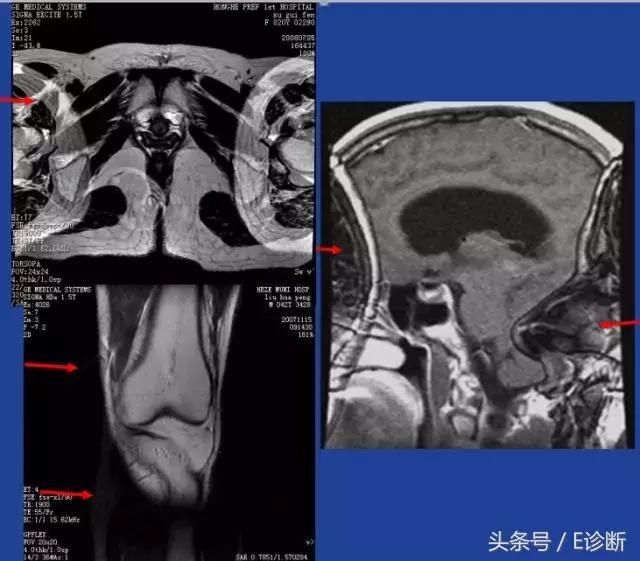

卷褶伪影

原因: 机器不能识别带宽以外的频率。任何超出范围外的频率将同带宽内的一个频率相“混叠”。

频率、相位方向均可出现,视野一侧FOV以外的信号叠加在另一侧的FOV内

3D也可出现在层面选择方向。最后一层可叠加到第一层。

加大FOV

NPW

饱和脉冲

3D舍弃开始与最后几个层面